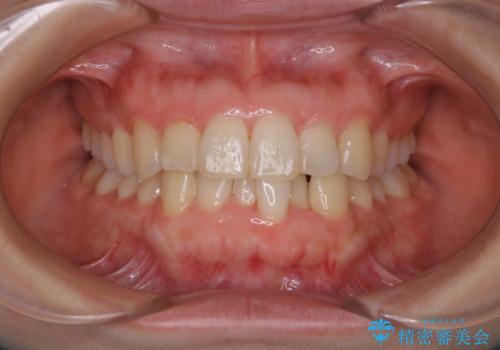

[ マウスピース矯正 ] 前歯のねじれを治したい

![[ マウスピース矯正 ] 前歯のねじれを治したいの症例 治療前](https://seimitsushinbi.jp/wp/wp-content/uploads/2022/01/IMG_1344-500x350.jpg?v=1641871025)